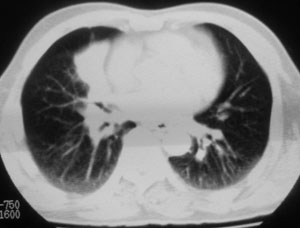

性别 男  62岁 因咳嗽及左肱骨剧烈痛疼数天来院检查。

右中央型肺癌并肱骨转移。

考虑右肺中叶肺癌并左肱骨转移伴病理性骨折。

支持右肺中心型肺癌并肺内及左肱骨转移伴病理性骨折

右肺中心型肺癌并中叶不张,左肱骨溶骨性转移并病理骨折。